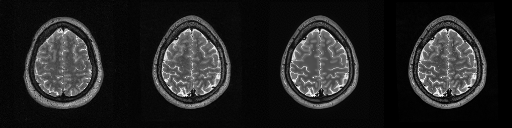

HCP T2w dataset

We utilize images from the publicly available Human Connectome Project (HCP) [51] T2-weighted (T2w) images dataset for the task of compressed sensing, which contains brain images from 47 patients. The HCP dataset includes cross-sectional images of the brain taken at different levels and angles.

Compressed sensing

We train a flow-based model from scratch on 10,000 randomly sampled images, utilizing the ncsnpp architecture [9] with minor adaptations for grayscale images. We employ compression rates , meaning . The measurement operator is given by a subsampled Fourier matrix, whose sign patterns are randomly selected. We evaluate our reconstruction algorithm’s performance on 200 randomly sampled test images.

We present the quantitative and qualitative results of compressed sensing in Tab. 1 and Fig. 4, respectively. As shown in Tab. 1, our method consistently achieves the best performance across varying compression rates . In Fig. 4, our method produces reconstructions that are more faithful to the original images, with fewer artifacts, leading to higher accuracy and clearer details.